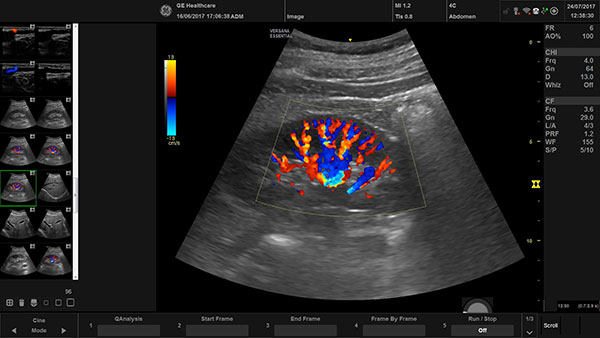

Doppler vascular ultrasound or a color Doppler ultrasound is a special ultrasound technique that allows the physician to see and evaluate blood low through arteries and veins in the abdomen, arms, legs, neck and/or brain (in infants and children) or within various body organs such as the liver or kidneys. Vascular ultrasound produces precise images and measurements of many blood vessels in the body. It can detect diseased vessels and identify a wide variety of changing conditions, enabling the radiologist to make a quick and accurate diagnosis.